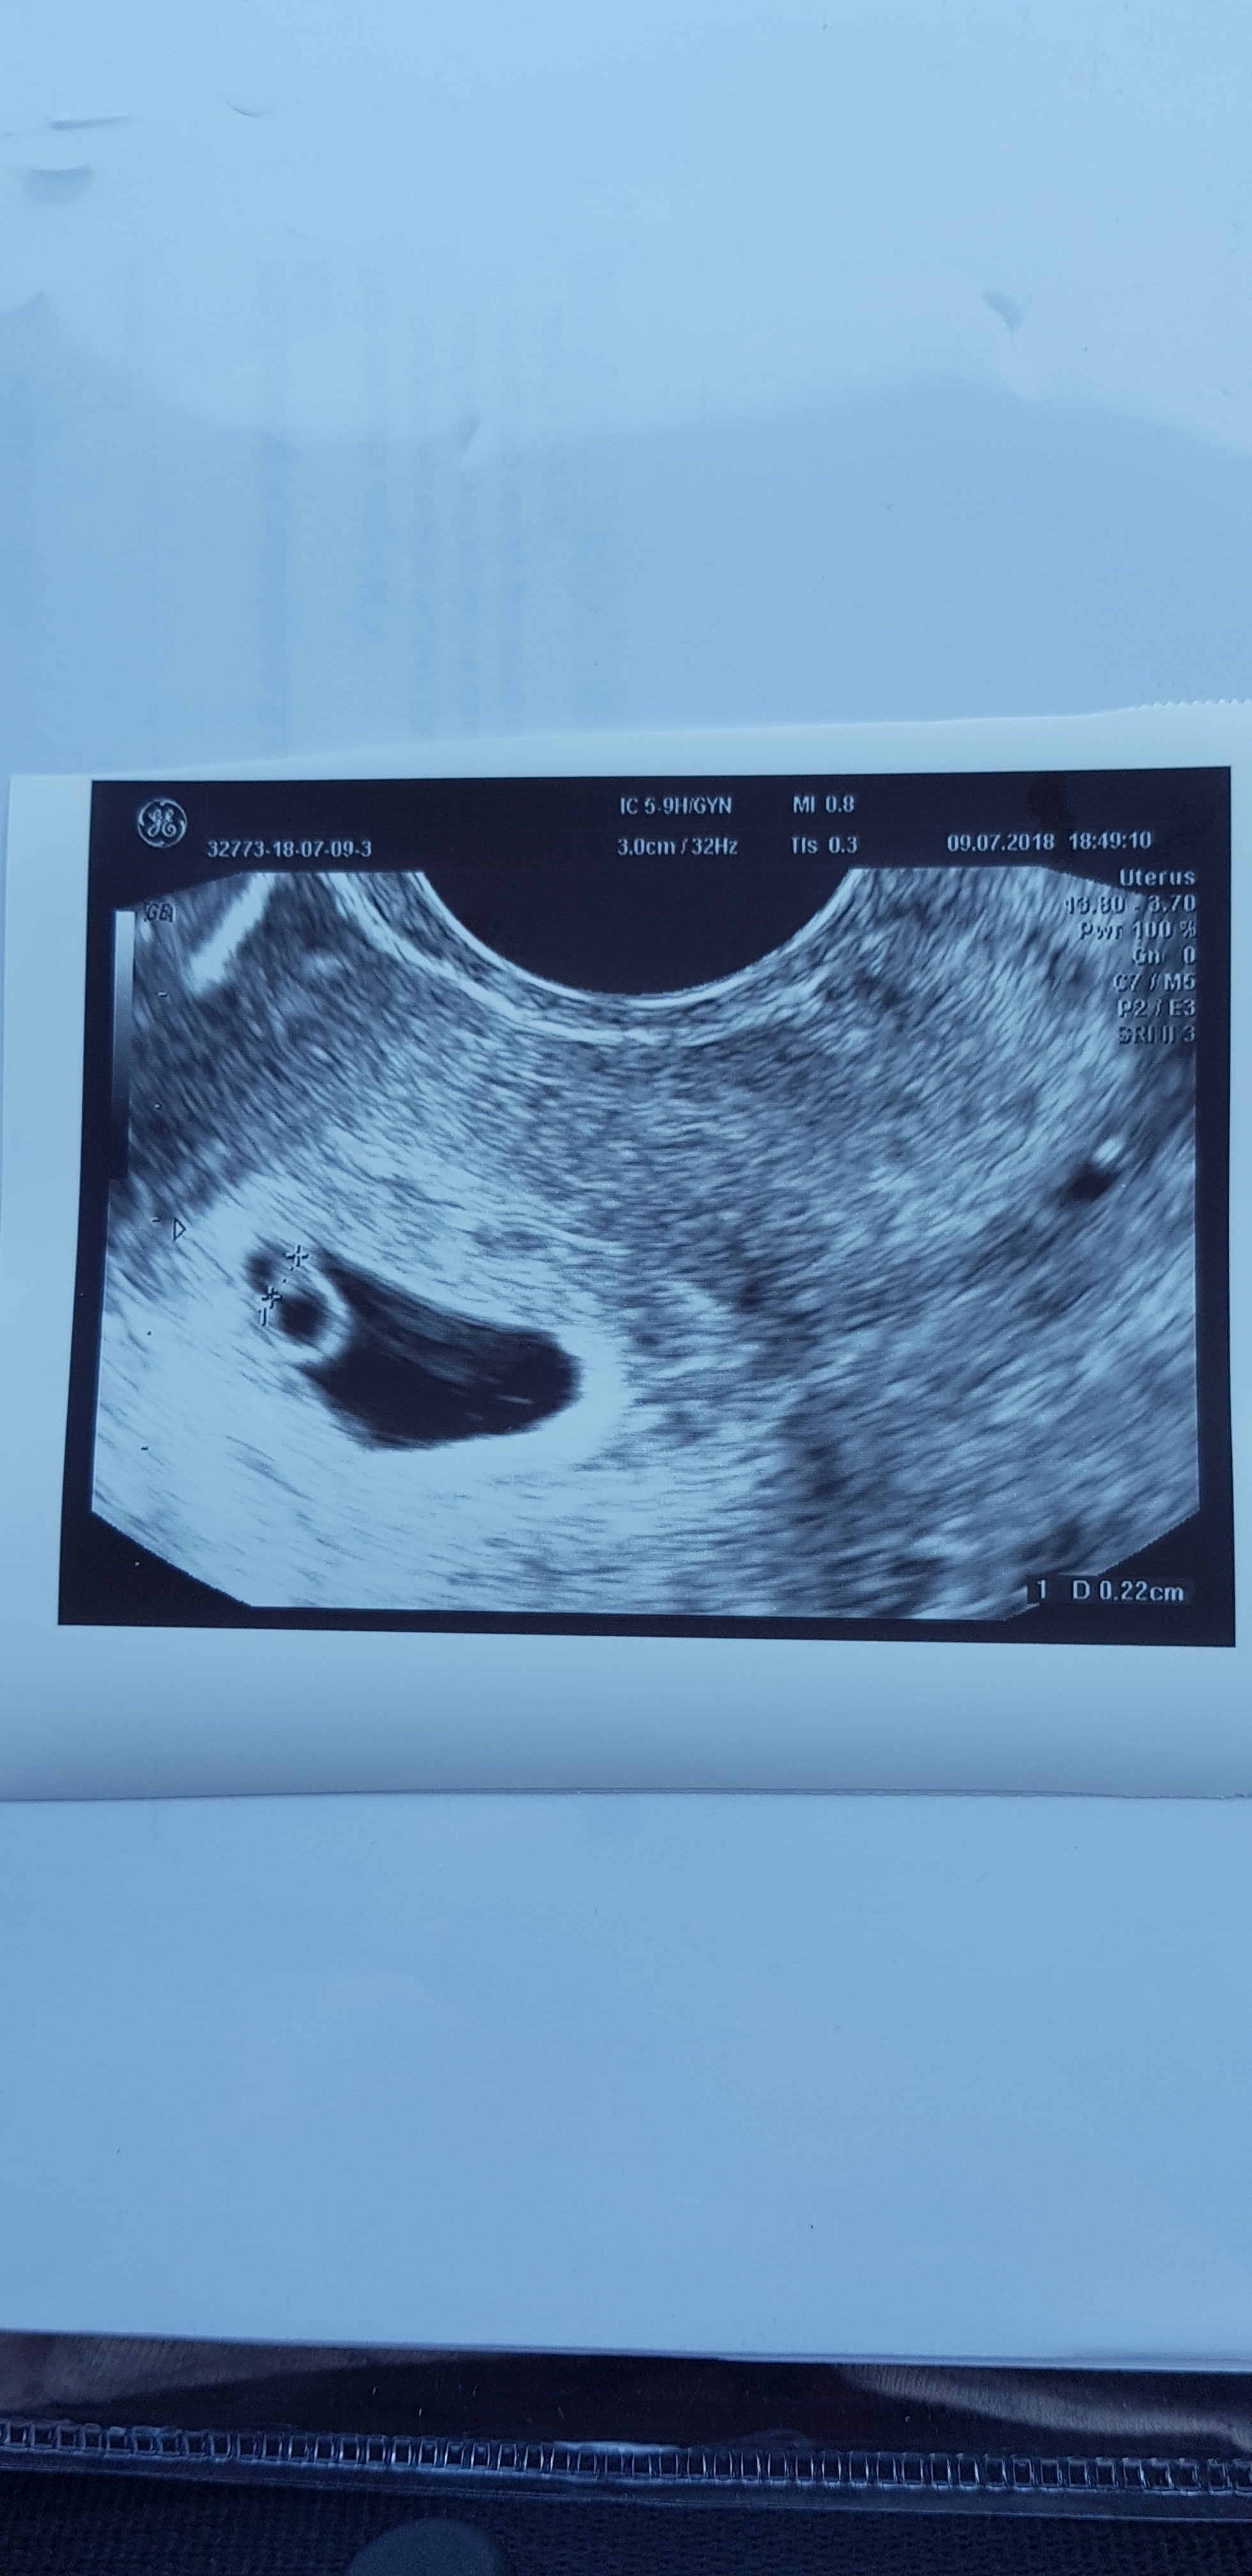

Jeszcze raz gratuluje niedowiarku :*Nasz maluszek ma 0.22mm I bijące serduszko

Cudownie! [emoji173][emoji173][emoji173][emoji173][emoji173]Nasz maluszek ma 0.22mm I bijące serduszko

GRATULACJENasz maluszek ma 0.22mm I bijące serduszko

gratulacje kochanaNasz maluszek ma 0.22mm I bijące serduszko

Wspanialeeeeeeeee [emoji173][emoji173][emoji173][emoji173][emoji173][emoji173]Nasz maluszek ma 0.22mm I bijące serduszko